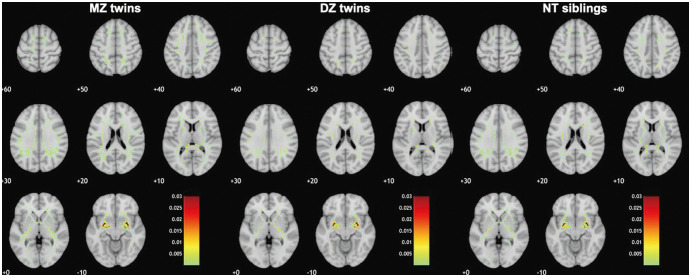

Results: The spatial similarity of dPVS was significantly higher in MZ twins [higher DS (median, 0.382 and 0.310) and SSIM (0.963 and 0.887) and lower MSE (0.005 and 0.005) for BGdPVS and WMdPVS, respectively] than in DZ twins [DS (0.121 and 0.119), SSIM (0.941 and 0.868), and MSE (0.010 and 0.011)] and NT siblings [DS (0.106 and 0.097), SSIM (0.924 and 0.848), and MSE (0.016 and 0.017)]. No significant difference was found between DZ twins and NT siblings. Similar results were found even after the subjects were matched according to dPVS volume. Regional dPVS volumes were also more correlated within pairs in MZ twins than in DZ twins and NT siblings.

Conclusion: Our results suggest that genetic factors affect the location of dPVS.